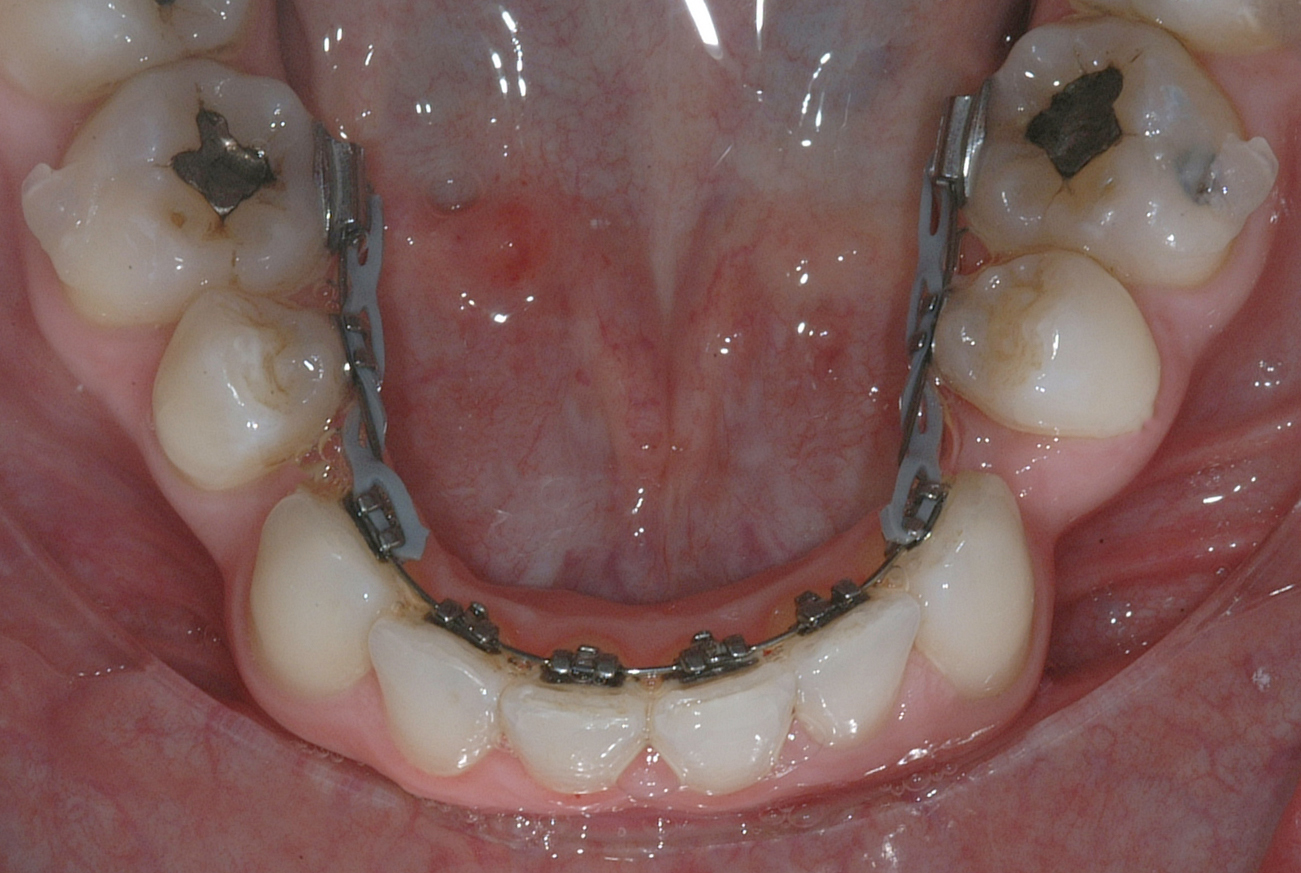

Per la chiusura dello spazio all’arcata inferiore, dopo la preliminare fase di allineamento e livellamento2, con la stessa sequenza iniziale di archi (.014” e poi .016” Nichel-Titanio), è stato temporaneamente applicato un sistema di ancoraggio ausiliario vestibolare, mediante fibre rinforzate, bondate sulla superficie vestibolare di 3.5, 3.6, 3.7 (Figura 4).

Successivamente, per controllare il movimento radicolare distale del canino inferiore sinistro (3.3), è stato applicato un sistema di forze che ha sfruttato: la forza singola distalizzante e di chiusura spazi data dalla catenella elastica con ruolo stabilizzante anche verticale su 3.3, inserita e agganciata in due segmenti, uno mesiale e uno distale, nelle rispettive alette dello slot occlusale del 3.3, e una coppia di forze di uprighting data dall’arco ortodontico .016” Nichel Titanio; quest’ultimo è stato inserito distalmente nello slot ausiliario dell’attacco linguale sul 3.5 ottenuto ripiegando verso occlusale la terza aletta gengivale, e poi nel tubo singolo sul 3.6, e mesialmente, da mesiale verso distale e da gengivale verso occlusale nello slot di 3.3, generando una flessione verticale di secondo ordine, la cui rotazione in senso linguale veniva controllata dalla catenella elastica stessa in appoggio su di esso. Il segmento di arco distale a 3.2 è stato ripiegato in senso gengivo-vestibolare (Figura 5).

Nota tecnica: una volta ottenuto il corretto posizionamento del 3.3, al fine di simmetrizzare l’arcata inferiore e centrare le linee di simmetria, è stata applicata una molla ad anse aperte tra 4.4 e 4.3 su arco .016” in acciaio (Figura 6).